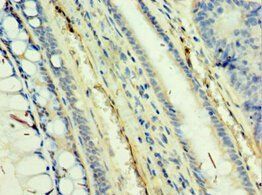

Immunohistochemical analysis of TAF5L staining in human breast cancer formalin fixed paraffin embedded tissue section. The section was pre-treated using heat mediated antigen retrieval with sodium citrate buffer (pH6.0). The section was then incubated with the antibody at room temperature and detected using an HRP conjugated compact polymer system. DAB was used as the chromogen. The section was then counterstained with haematoxylin and mounted with DPX.